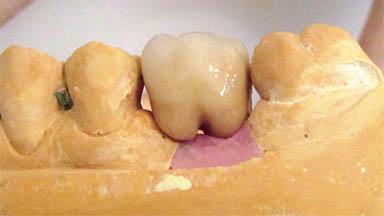

Management of a Fractured Implant Supporting a Screw-retained Metal-ceramic Restoration

The fracture of an implant after it has been restored is one of the most severe complications. It most frequently occurs in partially edentulous jaws (1.5%). Most implant fractures involve implants with a diameter of 3.75 mm made of commercially pure titanium (Eckert 2010). Unfortunately, many cases are not reported or documented by the clinicians involved in resolving the problems created by the fracture. This case report describes the management of an implant fracture at site 36 in a middle-aged male patient. The implant had been restored with a screw-retained metal-ceramic crown.